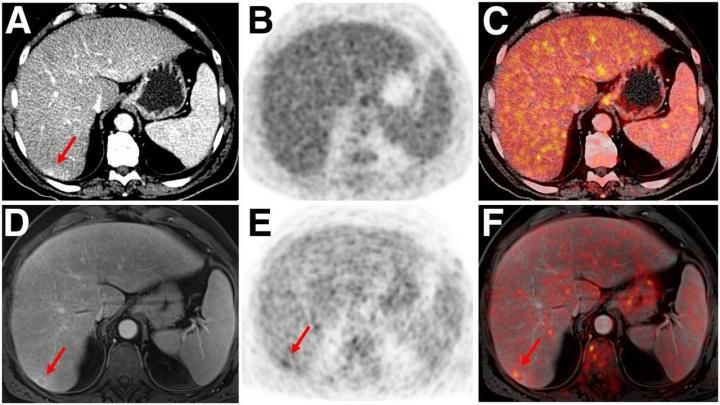

Pet Mri For Gastrointestinal Imaging Gastroenterology Clinics

Diagnostics Free Full Text Pet Mri In Oncological Imaging State Of The Art Html

Pet Mri Outperforms Pet Ct In Cancer Imaging